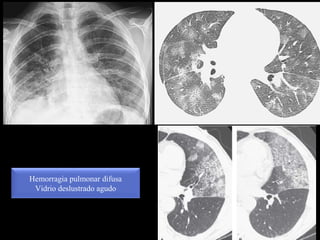

Vidrio deslustrado agudo

Hemorragia pulmonar difusa